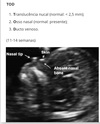

Aconselhamento genético O que o exame biofísico avalia?

Aconselhamento genético O que o teste duplo avalia?

Valor da translucência nucal ao USG que sugere síndrome de Down?

Perfil dos hormônios maternos que sugere síndrome de Down? (5)